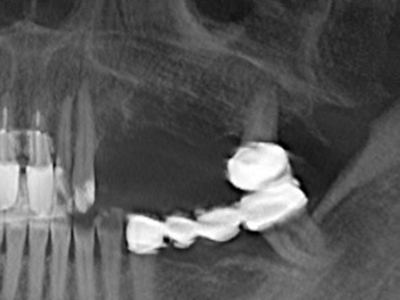

Fig. 17: Tomografía computarizada de un osteoma de crecimiento progresivo ...

Fig. 17b: justo al lado del canal alveolar con irritación nerviosa (vista lateral y coronal).

Fig. 18: Preparación de una tapa cortical con la sierra ósea piezoeléctrica (Piezomed, W&H).

Fig. 19: Zona operada después de neurolisis y eliminación del osteomo.

Fig. 20: La tapa ósea extraída se readapta y se fija mediante un tornillo para osteosíntesis (KLS Martin, Tuttlingen).